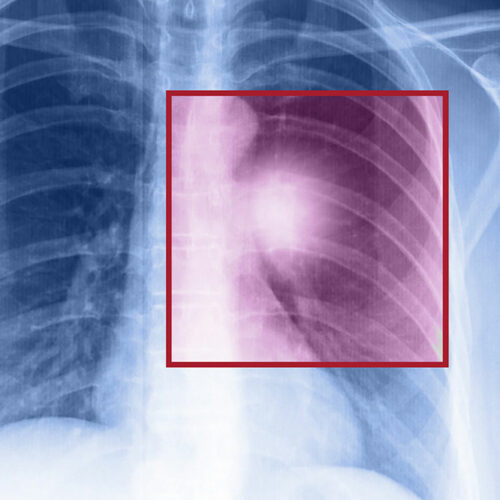

When the cells in the lungs begin to abnormally multiply and grow, it results in cancer. Lung cancer is one of the leading causes of death in the world. And the risk of suffering from this life-threatening disease is even higher when one is a smoker. Herein, we discuss the various factors that come into play when it comes to lung cancer.